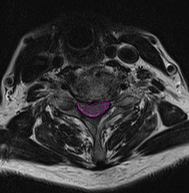

Στένωση αυχενικού σπονδυλικού σωλήνα με πίεση και παραμόρφωση του νωτιαίου μυελού.